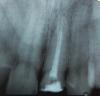

Kivilgar Опубликовано 8 марта, 2010 Поделиться Опубликовано 8 марта, 2010 В детстве была травма верхнего резца (№11), в возрасте 15 лет он сломался. Зуб был депульпирован и на корень была поставлена пломба по форме зуба. Со временем пломба пришла в негодность и я решил ее заменить на металокремику. Пломбу убрали, на снимке обнаружили затемнение в канале, сказали что канал запломбирован не на всю глубину. Вскрыли канал и перелечили его. Новым снимком остались довольны. Поскольку соседний зуб (№21) тоже нуждается в лечении (кариес) ортопед под установку коронки пока этот зуб не берет, поэтому пришлось вновь записаться к терапевту, но уже только через неделю. Сейчас зуб с открытым корнем, т.е. там было что-то напоминающее временную пломбу, но она частично выкрошилась (и это за 2 дня после его установки и при отсутствии воздействия на нее!!!). Стоит ли поторопиться с закрытием корня зуба (возможно сменив врача-терапевта) или 5-6 дней с открытым корнем некритично?Снимок не очень четкий,пломбировка канала плохо видна Врач говорил про изменения в кости около корня или их нет?, а то тут ничего не видно. Ссылка на комментарий

leon737 Опубликовано 8 марта, 2010 Автор Поделиться Опубликовано 8 марта, 2010 (изменено) Да, терапевт сказал, что канал запломбирован не до конца. Его перепломбировали и заверили меня, что изменений в кости в области канала нет, и теперь вполне можно установить штифт под коронку. Снимок нечеткий, т.к. никак не удавалось сделать его на короткой экспозиции с рук. Делал как советовали на этом форуме - положил снимок на экран монитора, вывел яркость по-больше и снял его на белом фоне. Вот, переснял с упора. Кстати, у меня во рту постоянный привкус какого-то лекарства. Может быть такое, что оно вымывается из канала? Изменено 8 марта, 2010 пользователем leon737 Ссылка на комментарий

Бело4ка Опубликовано 8 марта, 2010 Поделиться Опубликовано 8 марта, 2010 Канал запломбирован не герметично. Много пустот и пор. Надо перелечивать опять. Тем более если планируется протезирование. Ссылка на комментарий